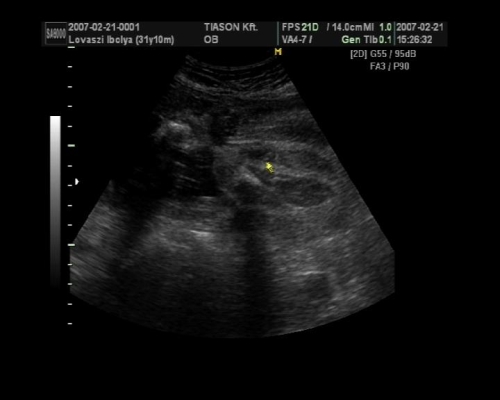

, de ami fura volt, a szívét a pocakom bal oldalán középtájban éreztem, felette pedig folyamatos rugdosást, vagy kalimpálást, De a másik oldalon ugyanott szintén... Lehet, hogy keresztben van???? De a múltkor már lent volt. Na kíváncsi vagyok kedden mit mutat az UH. Dehát azt csak lehetne látni rajtam, ha keresztben lenne...